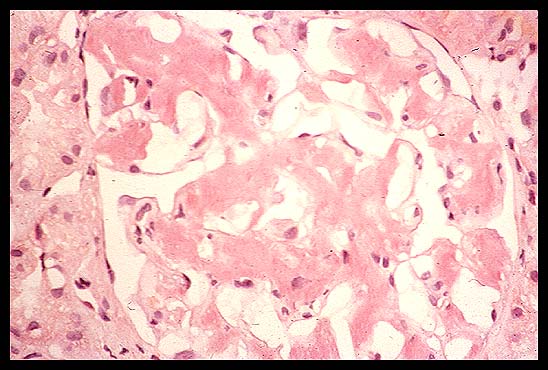

Glomerulopathy with non-amyloid MIDD

They can also have a glomerulopathy. And they can have a nodular glomerulopathy which looks just like diabetes. Before the days of standardized staining for light chains, a patient with this could be potentially mistaken for someone with diabetes, except for the fact that the history is such in most of these patients that they obviously don't have diabetes.

So when you see diabetic nodular glomerulosclerosis in a nondiabetic, think about light chain deposition disease. I don't know how many of your pathology departments do standardized light chain immunofluorescence, but we started doing them about 12 or 13 years ago because you'll miss these patients. Now granted, the yield isn't high. But nonetheless, this is the only way you are going to pick them up. And not all of them have this nodular glomerular sclerosis. Some of them can have just nonspecific glomerular findings.